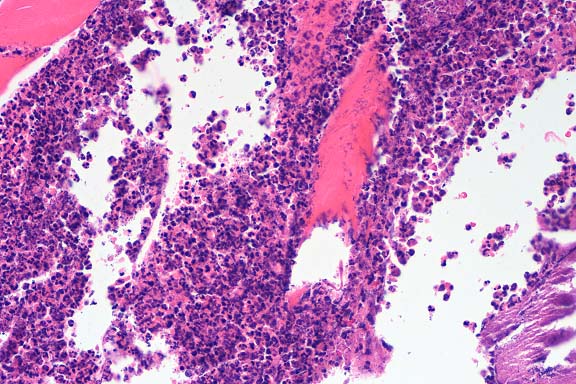

SJL mice are an inbred line derived from Swiss Webster mice and have been used to study autoimmune diseases (experimental autoimmune encephalomyelitis, experimental thyroiditis, experimental interstitial nephritis, and autoimmune myositis) as well as lymphosarcoma (formerly called reticulum cell sarcoma). Ninety percent of SJL mice spontaneously develop lymphosarcoma by 12 months of age, and nearly 100% develop myositis by eight months.

Lymphosarcoma begins in mesenteric lymph nodes and Peyer's patches and has considerable morphologic variability, even at different sites within a single animal. The neoplasia is derived from a B lymphocyte but is dependent on T-cell cytokines (IFN-g, IL-2) for continued growth. A significant finding in the pathogenesis was the discovery that neoplastic B lymphocytes expressed a portion of endogenous mammary tumor virus antigen that is a superantigen for Vb16 T-cells, resulting in their stimulation. Consequently, lesions contain mixtures of neoplastic B-cells, reactive T-cells and B-cells, and activated macrophages, including multinucleate giant cells.

Conference Note: The SJL mouse is an inbred strain with a high incidence of spontaneous malignant lymphomas of the B-cell type often involving multiple abdominal organs. A recent study in SJL mice indicates that the histologic appearance of lymphomas from various sites may be heterogenous, even when there is clonal identity. Lymphomas arising in multiple organs within one mouse are usually derived from a single clone but may show development of subclones within a major clonal population. This finding is consistent with the concept that clonal evolution is a common event in the course of lymphoid neoplasia.